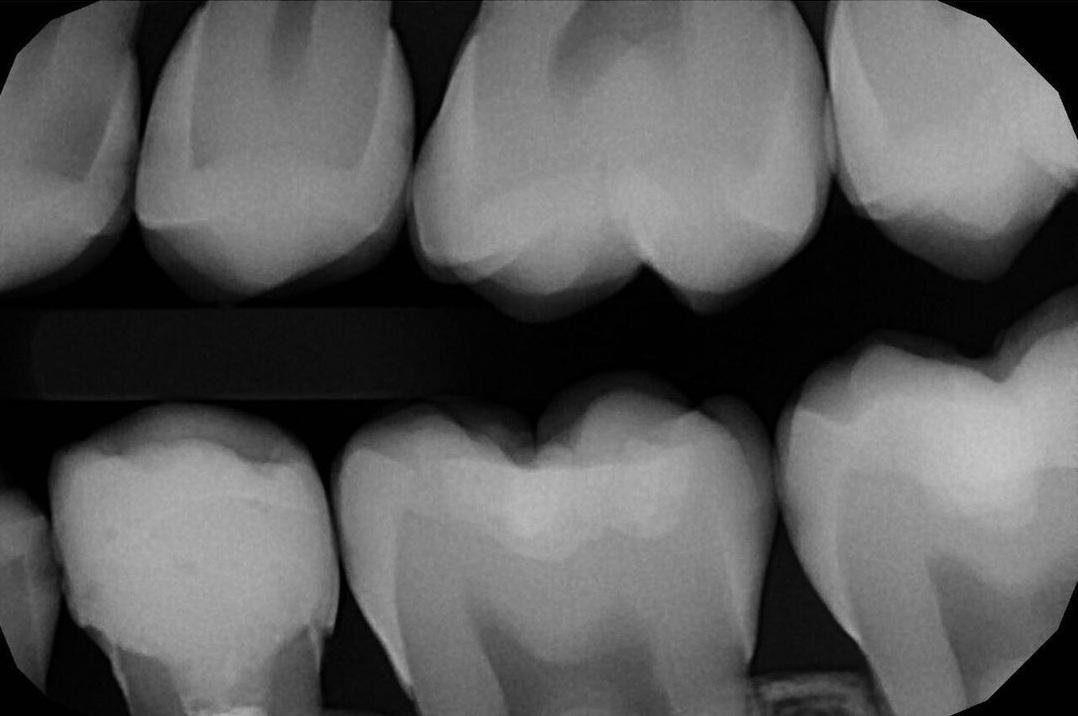

Прицельные внутриротовые снимки.

Прицельные интерпроксимальные снимки.

Интерпроксимальные снимки, где на один снимок помещается сразу восемь контактных поверхностей, делают редко, а они важные, потому что видно кариес самый-самый маленький. КТ помогает увидеть все зубы в объёме, в повороте, видно все воспаления. Телерентгенограмму делают в основном ортодонты или при сложном ортопедическом лечении. Это специальное исследование для проведения антропометрических исследований, то есть оно даёт снимок головы один к одному, и можно проводить угловые измерения величины. Фотопротокол важен для сравнений до и после, потому что это важно и пациенту, и врачу для обучения. Если фотопротокола нет, то через несколько лет будет сложно восстановить картину.